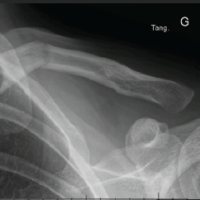

- Standard radiographs: Appeared normal (Fig. 1a)

Figure 1: (a) Representative radiograph demonstrating normal appearance. (b) Transverse magnetic resonance imaging (MRI) image showing high signal intensity within the peroneus brevis tendon at the lateral malleolar level (red arrows). The peroneus longus tendon (blue arrows) appears normal. (c) Coronal MRI image demonstrating a longitudinal tear in the peroneus brevis tendon. (d) Sagittal MRI image demonstrating the longitudinal tear in the peroneus brevis tendon (red arrows) and a normal peroneus longus tendon (black arrow).